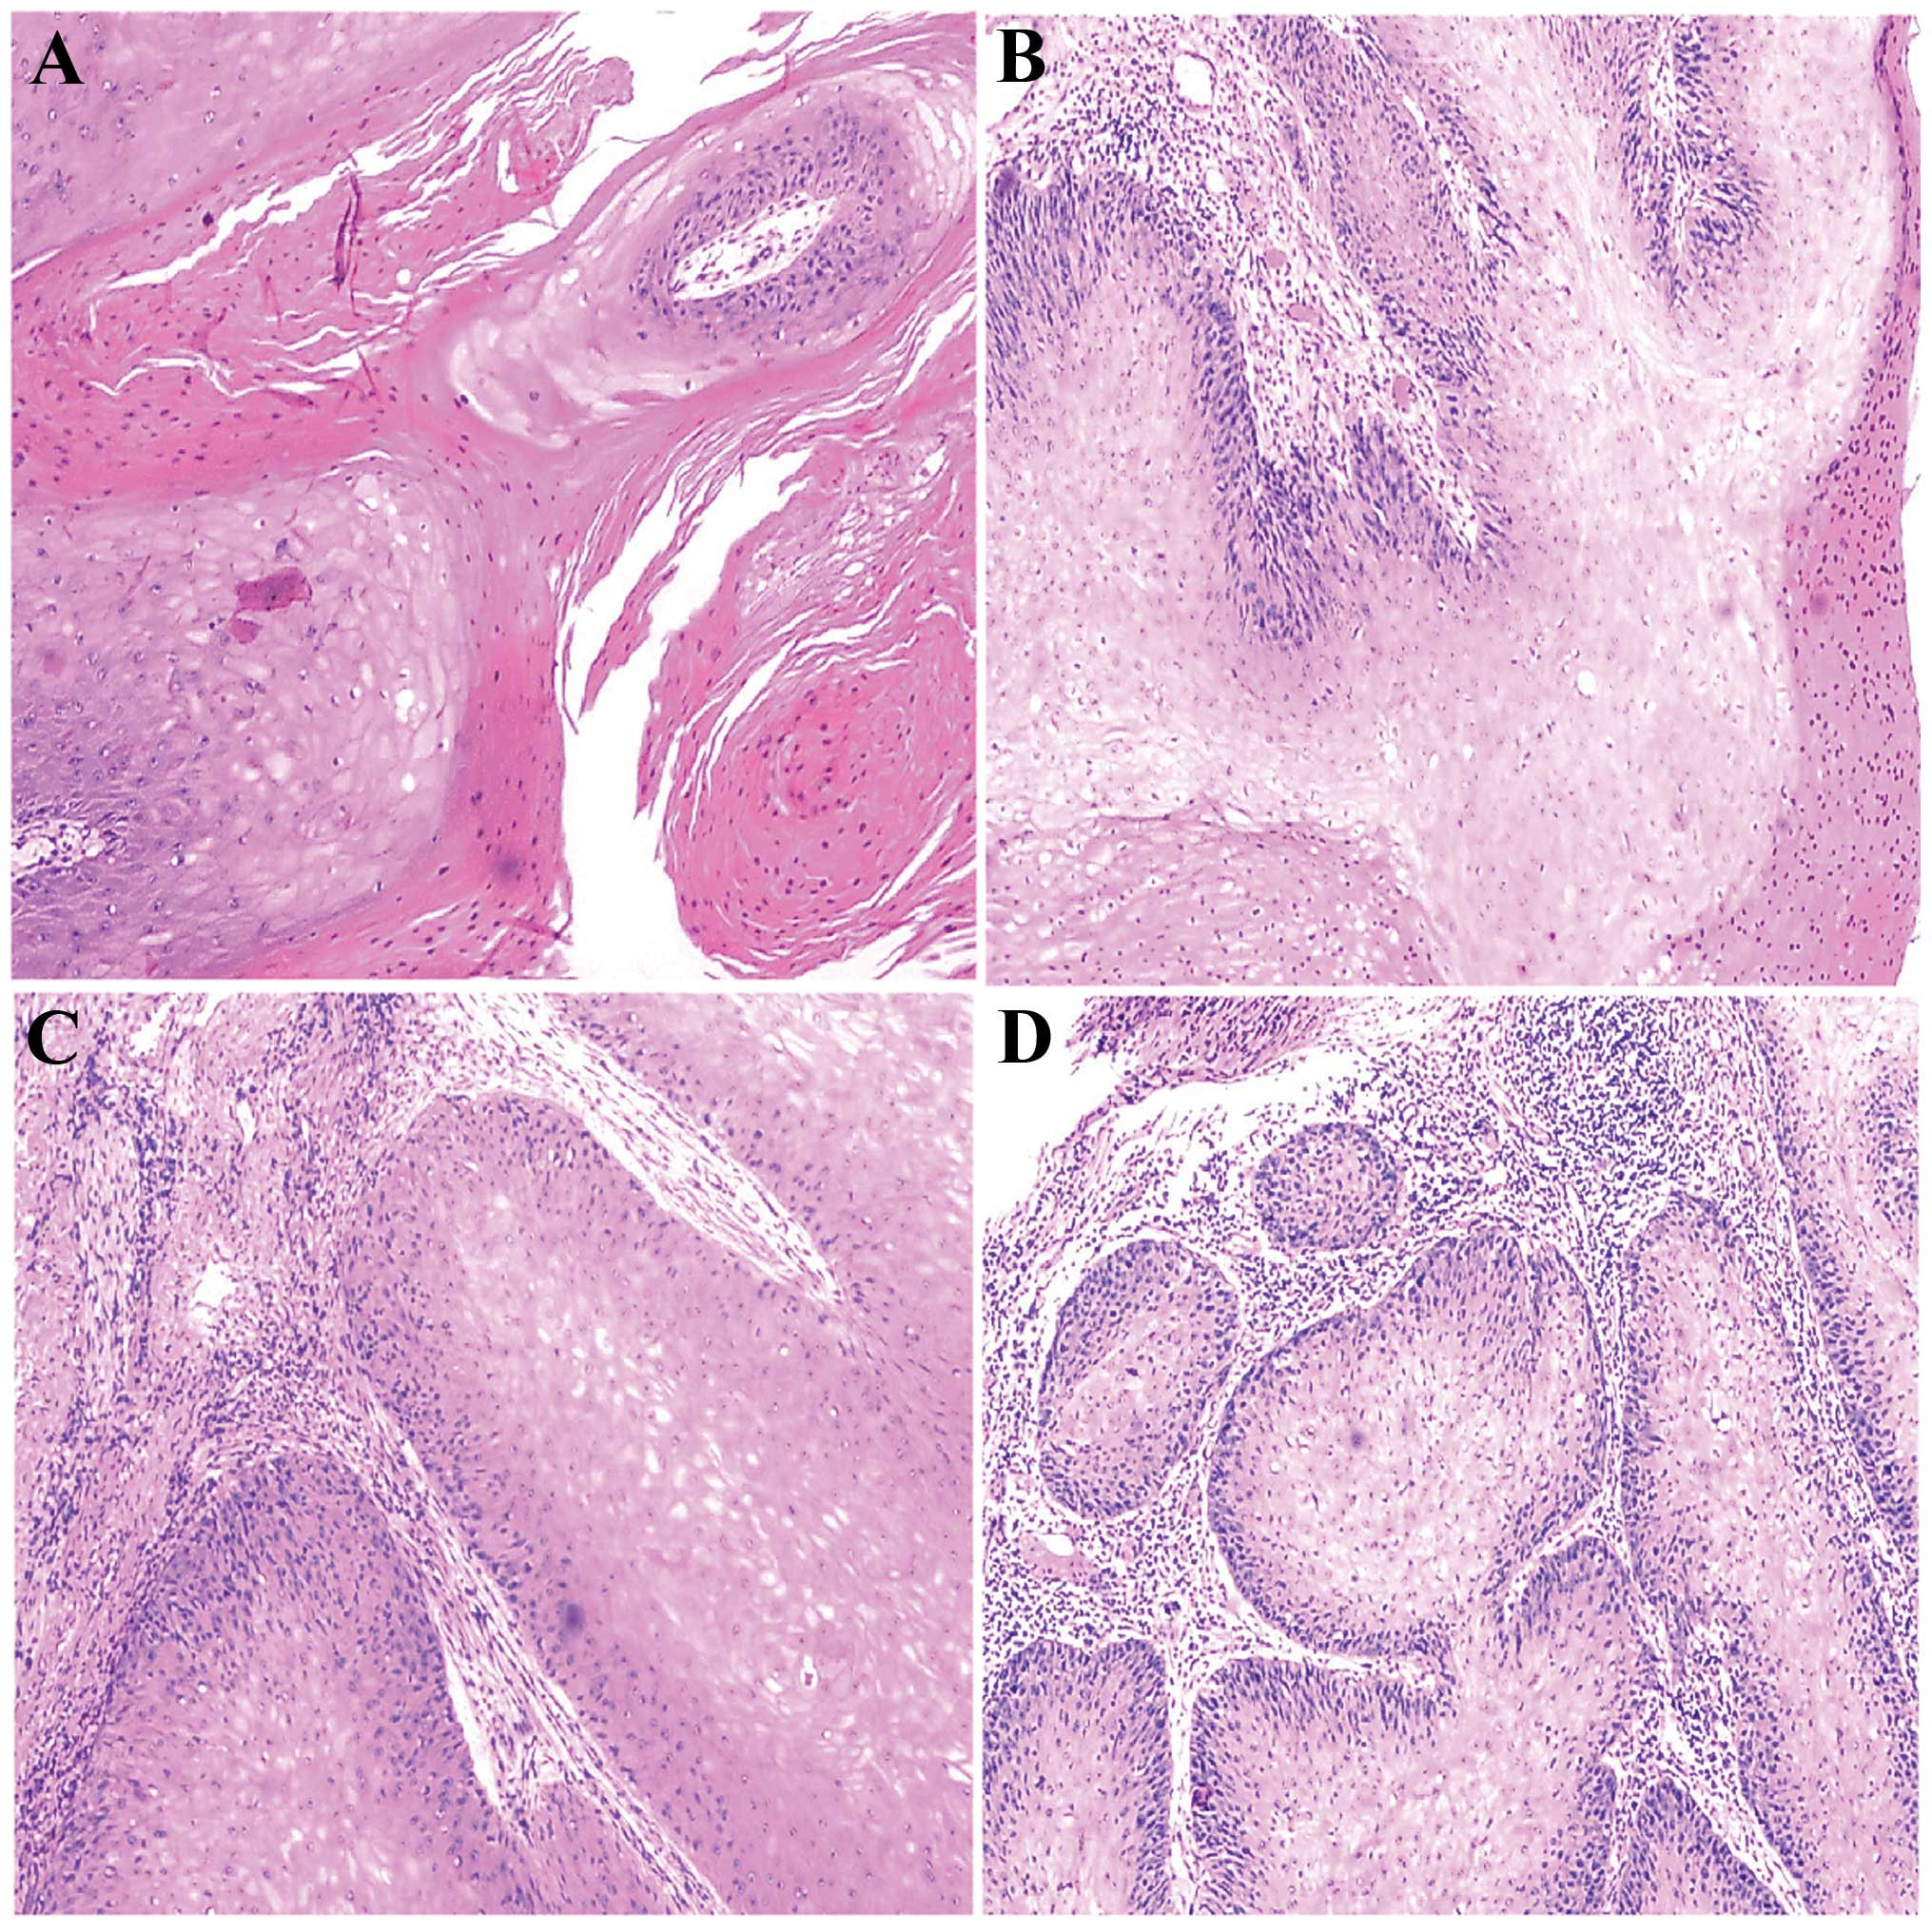

penile cancer photos download

Posts: penile cancer photos download